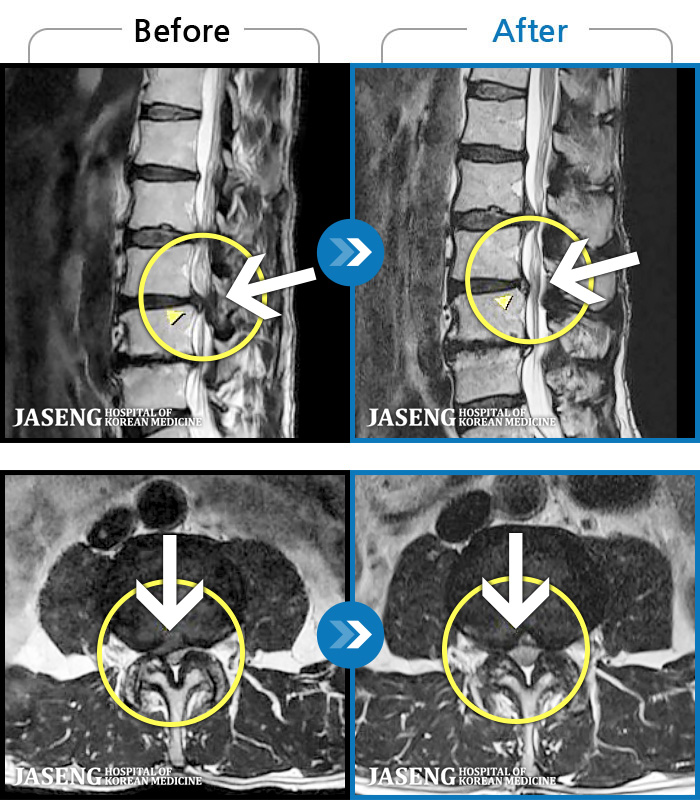

MRI ġ

1,237 MRI ũ ʸ Ȯϼ.